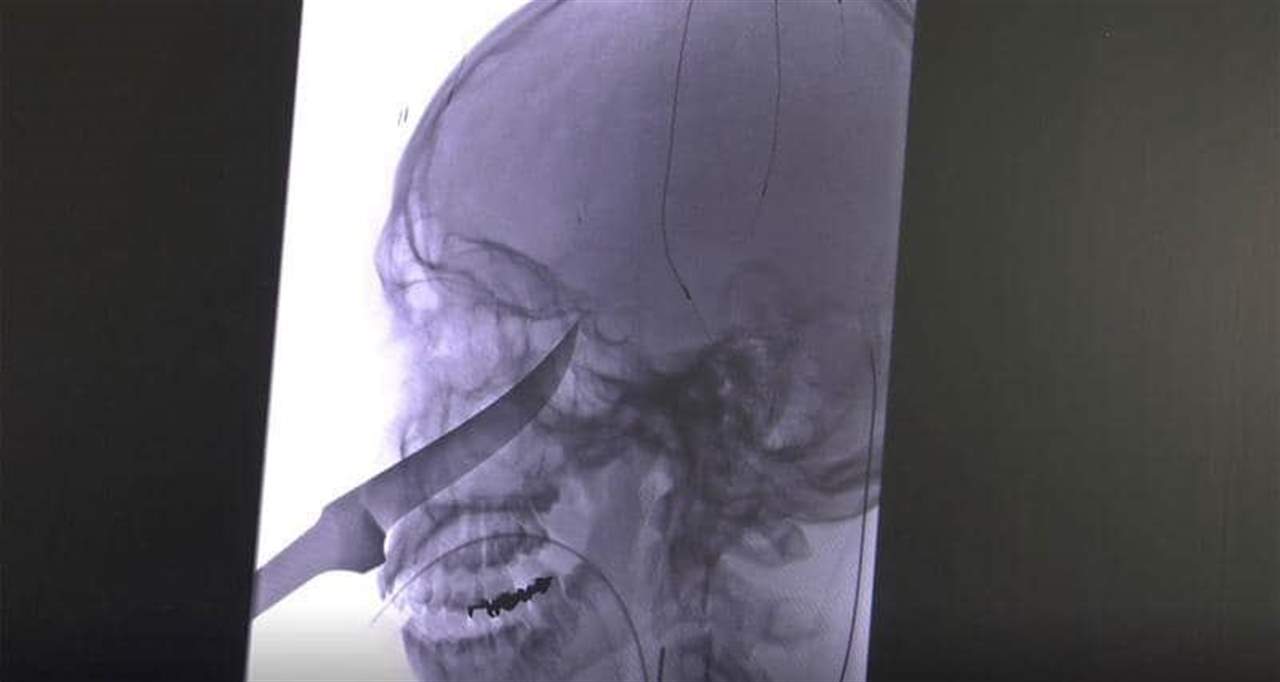

نجح فريق طبي أميركي في إنقاذ حياة مراهق من ولاية كانساس، تم نقله إلى المستشفى بينما كان سكين طوله 25 سنتيمترا يخرج من جمجمته.

ونقل موقع "فوكس نيوز" عن جيمي راسل، والدة إيلي غريغ، قولها إنها كانت تتناول العشاء عندما سمعت أطفالها يلعبون بالخارج، وسمعت ابنها البالغ من العمر 15 عاما يصرخ.

وأضافت الوالدة التي لا تزال على غير علم بكيفية إصابة ابنها: "في البداية اعتقدت أن الصراخ طبيعي، ثم جاء إيلي إلى الباب وعندما فتحه كان وجهه عبارة عن كتلة من الدم وقطعة معدنية تخرج منه، كان الأمر صادما للغاية".

وتابعت: "اعتقدت أنه قضيب معدني، وبعد ذلك استطعت أن أرى أنه يشبه مقبض سكين وهذا ما كان عليه فعلا، وفكرت مباشرة بالاتصال بالشرطة".

وفي مستشفى ميرسي للأطفال في كانساس، هرع المسعفون حيث رأى الأطباء احتمال تلف الشريان السباتي في دماغه، الأمر الذي كان سيؤدي إلى الإصابة بالسكتة الدماغية أو أضرار جسيمة، فقرر الأطباء نقله إلى نظام الصحة بجامعة كانساس، حيث تمكن فريق طبي في أقل 24 ساعة من إنقاذ إيلي، الذي يخضع حاليا للعلاج بمجموعة من المضادات الحيوية واللقاح ضد الكزاز (التيتانوس)، فيما أمره الأطباء بالابتعاد عن أي أشياء حادة.